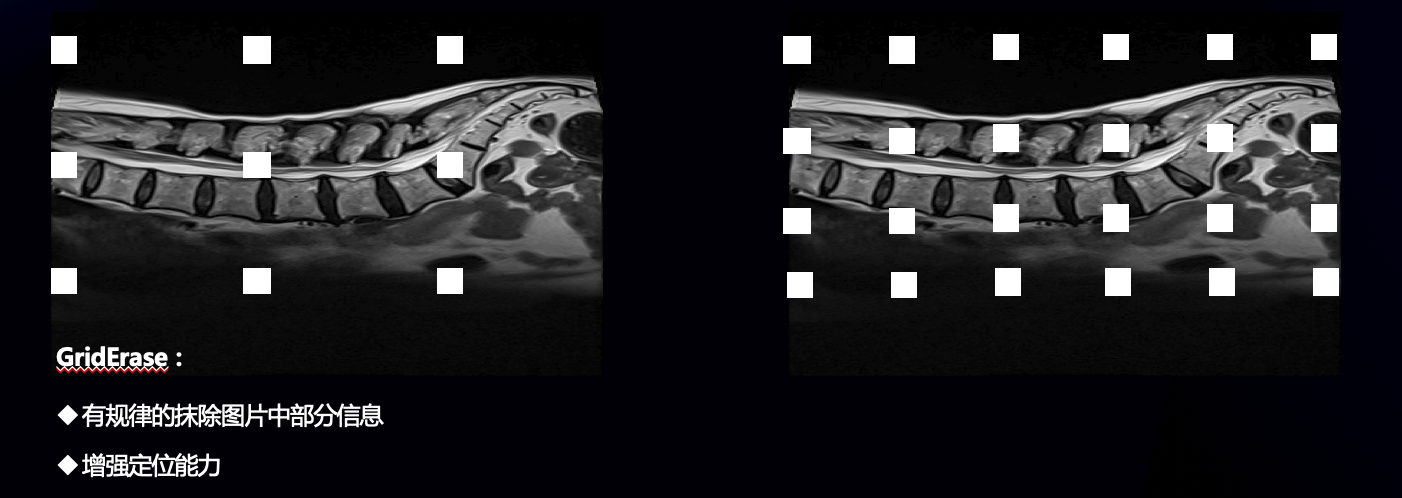

- 数据增强方面,我们采用了griderase

- 模型方面,采用经典的faster r-cnn ,纯pytorch版本,backbone为r50,从而适应cpu训练,具体细节上采用了fpn、多尺度训练和预测、以及bbox voting